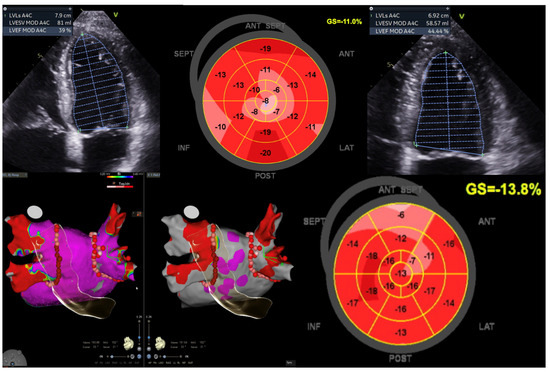

Figure 4. Illustration of LV function improvement (EF 44.4%, GLS −13.8%) in a 52-year-old male diagnosed with Tachy-Brady syndrome with LV dysfunction (EF 39%, GLS −11%), who underwent dual chamber pacemaker-left bundle branch area pacing, followed by atrial fibrillation ablation (pulmonary vein isolation). This case underscores the significance of conduction system pacing and echocardiography when using a global longitudinal strain (GLS) assessment for evaluating improvement in LV function. Image sourced from the Canberra Heart Rhythm Centre.